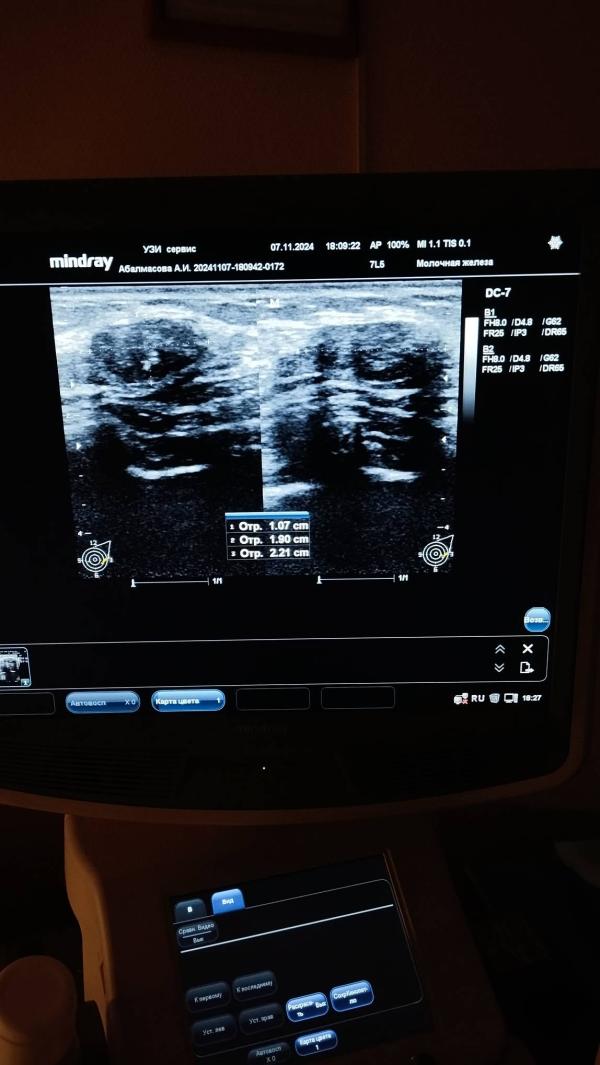

Фиброма: насколько это опасно? Разбираемся в причинах и методах лечения, что нужно знать

Есть те кто разбираются, просто фиброма , не может же быть ничего страшного да?

По описанию похожа, но точно врач только скажет. Возможно биопсию предложит сделать